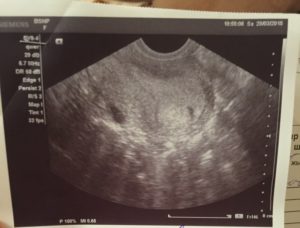

Этот вид ультразвукового исследования показывает наличие плода на максимально раннем сроке. Он проводится с помощью специального датчика, который вводят женщине непосредственно во влагалище, надев перед этим на него презерватив.

Точность такого метода объясняется тем, что датчик подходит максимально близко к органам малого таза, и отделен от них только стенкой влагалища. Данный метод исследования дает возможность зафиксировать появление плодного яйца уже с 3-й гестационной недели.

Но даже обнаружение такого плодного яйца не дает 100% гарантии того, что женщина беременна, так как оно попросту может быть пустым. А вот услышать сердцебиение плода и убедиться в том, что женщина все-таки беременна, можно примерно на 5-ой неделе.